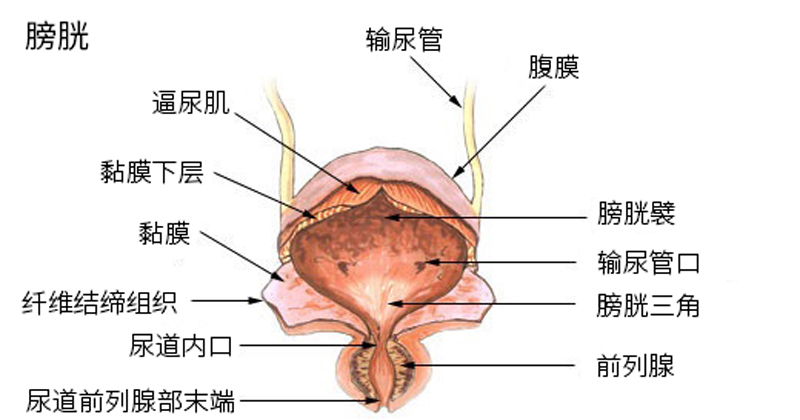

泌尿系統的解剖學差異

男生與女生的泌尿系統在結構上存在顯著差異,這直接影響排尿控制的能力。

男生尿道長約15-20厘米,從膀胱頸部延伸,經過前列腺、盆底肌群,最終至陰莖末端。尿道分為三段:前列腺尿道、海綿體尿道與膜尿道。其中,前列腺周圍有內括約肌(內尿道括約肌,為平滑肌,受自主神經控制)和外括約肌(外尿道括約肌,為骨骼肌,可任意控制)。這些括約肌確保尿液在適當時機排出。女生尿道則較短,僅約3-5厘米,從膀胱頸部直接延伸至陰道前壁開口。女生同樣擁有內外括約肌,但由於尿道短且靠近陰道與直腸,外部壓力(如懷孕或分娩)更容易影響控制。

根據解剖學描述,男生尿道較長確實提供額外阻力,但這並非「說停就停」的首要原因。關鍵在於外括約肌的強度與盆底肌群的協調。研究顯示,兩性皆可透過收縮盆底肌(Kegel運動)中斷尿流,但女生因解剖位置,較易受激素變化影響而導致肌力減弱。

女性的尿道開口在陰唇內,並非像男性一樣離身體有一段距離,而且尿道的方向向下。